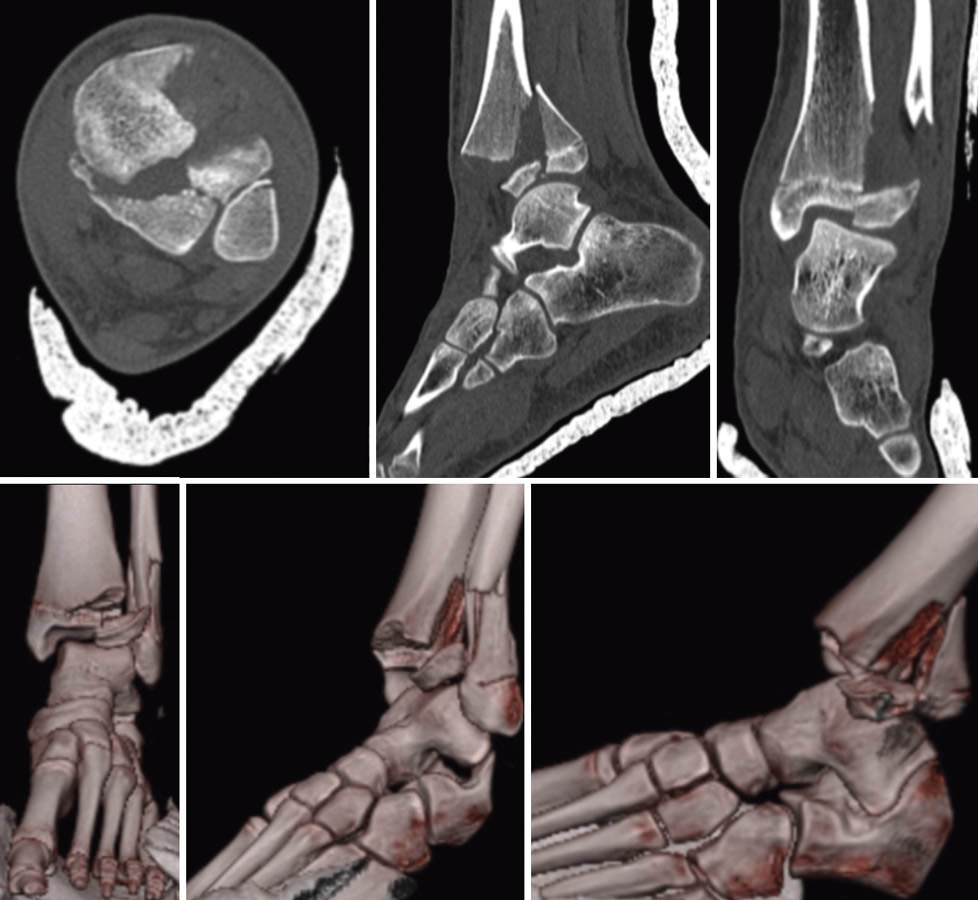

Se realizó una TC del tobillo que confirmó el diagnóstico de fractura triplanar en 3 fragmentos con fractura de peroné con ligero desplazamiento (Figura 2).

Figura 2. Tomografía computarizada + reconstrucción 3D: signo de Mercedes-Benz. Fractura Salter-Harris de tipo III en anteroposterior y de tipo II en proyección sagital + fractura de peroné.

Lo prioritario en toda fractura de tobillo durante el crecimiento es la reducción anatómica evitando manipulaciones repetidas. En el planteamiento terapéutico debemos considerar 3 aspectos fundamentales: el tipo de lesión según Salter y Harris, el mecanismo de producción y el crecimiento remanente del paciente. Se recomienda la realización de una tomografía computarizada (TC) en la que se visualiza la típica configuración en estrella de Mercedes-Benz(5) con reconstrucción multiplanar para realizar una buena planificación quirúrgica(6)(7).